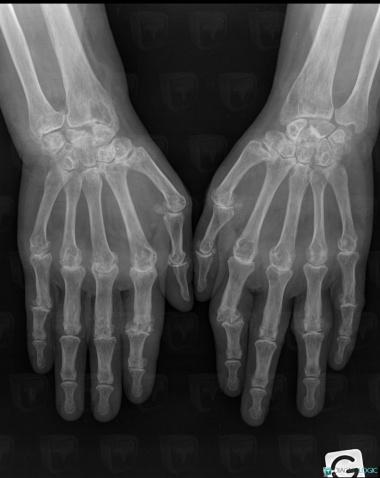

Rheumatoid arthritis, Radius - Distal part, Mediocarpal joint, X rays

- Diagnosis Rheumatoid arthritis, Location(s) Carpometacarpal joint, with gamuts Arthritis with osteoporosisInterphalangeal joint - Hand, with gamuts Arthritis with osseous production, Arthritis with deformityMetacarpophalangeal joints, with gamuts Arthritis with osteoporosis, Arthritis with deformityRadius - Distal part, with gamuts Epiphyseal osteolysisMediocarpal joint, with gamuts Radio/Ulno carpal joint, with gamuts Arthritis with osteoporosis

- Diagnosis Rheumatoid arthritis (link to Inflammatory arthritis), Location(s) Phalanx / Sesamoid bones - Hand, with gamuts Phalangeal osteolytic lesionScaphoid, with gamuts Sclerotic lesion in handOther carpal bones, with gamuts Sclerotic lesion in hand